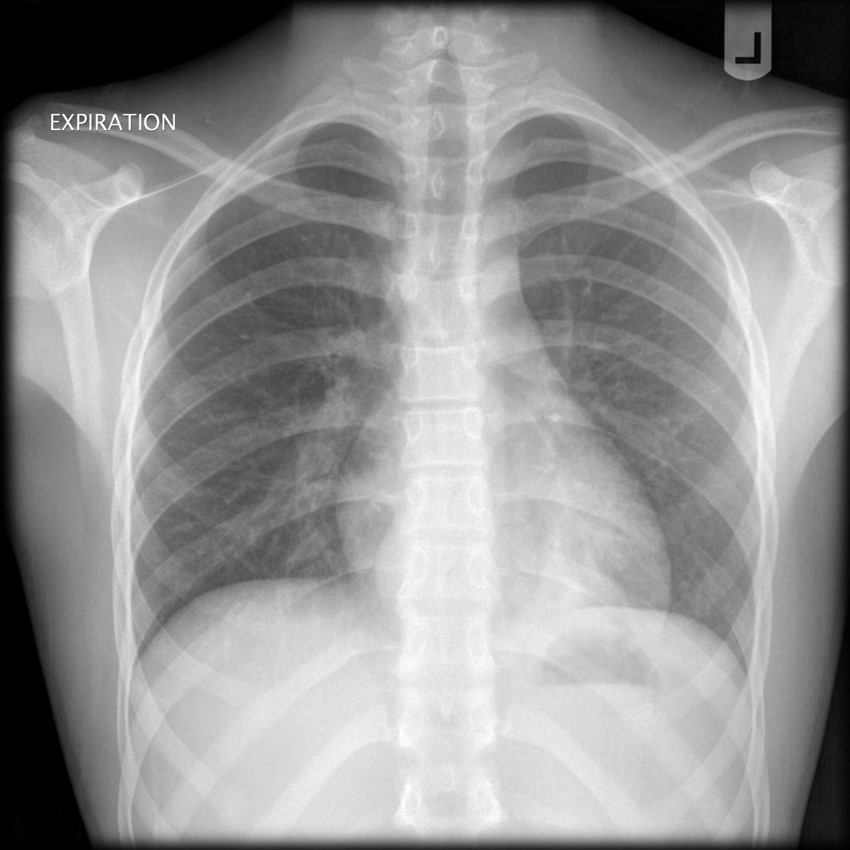

what is this? when would you take this?

expiratory AP

looking for pneumothorax